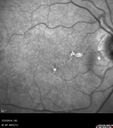

Retinal Arterial Macroaneursym390 views69 year old female with vision loss for a few months in the right eye. Images show a macroaneurysm in the right eye. The lesion had bled and FA showed no leakage. No treatment was done. VA improved from 20/40 - 20/32

Retinal Arterial Macroaneursym385 views69 year old female with vision loss for a few months in the right eye. Images show a macroaneurysm in the right eye. The lesion had bled and FA showed no leakage. No treatment was done. VA improved from 20/40 - 20/32

Retinal Arterial Macroaneursym373 views69 year old female with vision loss for a few months in the right eye. Images show a macroaneurysm in the right eye. The lesion had bled and FA showed no leakage. No treatment was done. VA improved from 20/40 - 20/32

Retinal Arterial Macroaneursym263 views69 year old female with vision loss for a few months in the right eye. Images show a macroaneurysm in the right eye. The lesion had bled and FA showed no leakage. No treatment was done. VA improved from 20/40 - 20/32

Retinal Arterial Macroaneursym257 views69 year old female with vision loss for a few months in the right eye. Images show a macroaneurysm in the right eye. The lesion had bled and FA showed no leakage. No treatment was done. VA improved from 20/40 - 20/32

Retinal Arterial Macroaneursym246 views69 year old female with vision loss for a few months in the right eye. Images show a macroaneurysm in the right eye. The lesion had bled and FA showed no leakage. No treatment was done. VA improved from 20/40 - 20/32

Retinal Arterial Macroaneursym237 views69 year old female with vision loss for a few months in the right eye. Images show a macroaneurysm in the right eye. The lesion had bled and FA showed no leakage. No treatment was done. VA improved from 20/40 - 20/32

Retinal Arterial Macroaneursym236 views69 year old female with vision loss for a few months in the right eye. Images show a macroaneurysm in the right eye. The lesion had bled and FA showed no leakage. No treatment was done. VA improved from 20/40 - 20/32

Retinal Arterial Macroaneursym230 views69 year old female with vision loss for a few months in the right eye. Images show a macroaneurysm in the right eye. The lesion had bled and FA showed no leakage. No treatment was done. VA improved from 20/40 - 20/32

Retinal Arterial Macroaneursym229 views69 year old female with vision loss for a few months in the right eye. Images show a macroaneurysm in the right eye. The lesion had bled and FA showed no leakage. No treatment was done. VA improved from 20/40 - 20/32

Retinal Arterial Macroaneursym227 views69 year old female with vision loss for a few months in the right eye. Images show a macroaneurysm in the right eye. The lesion had bled and FA showed no leakage. No treatment was done. VA improved from 20/40 - 20/32

Retinal Arterial Macroaneursym225 views69 year old female with vision loss for a few months in the right eye. Images show a macroaneurysm in the right eye. The lesion had bled and FA showed no leakage. No treatment was done. VA improved from 20/40 - 20/32